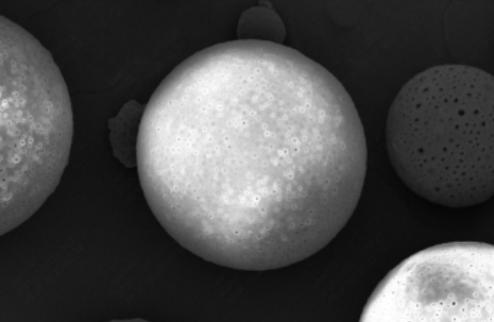

Vita Spire has developed HAp microsphere products for next-generation aesthetic fillers. We offer three different products, each varying in porosity, which corresponds to different degradation rates after injection. Our HAp microspheres provide versatile options for creating specialized, high-quality aesthetic treatments.

| Image | Cat. No. | Product Name | Features | Action |

|---|---|---|---|---|

| HAPAI-01 | Hydroxyapatite (HAp) Microspheres for Aesthetic Injection, Type I | N/A | Details |

| HAPAI-02 | Hydroxyapatite (HAp) Microspheres for Aesthetic Injection, Type II | N/A | Details |

| HAPAI-03 | Hydroxyapatite (HAp) Microspheres for Aesthetic Injection, Type III | N/A | Details |